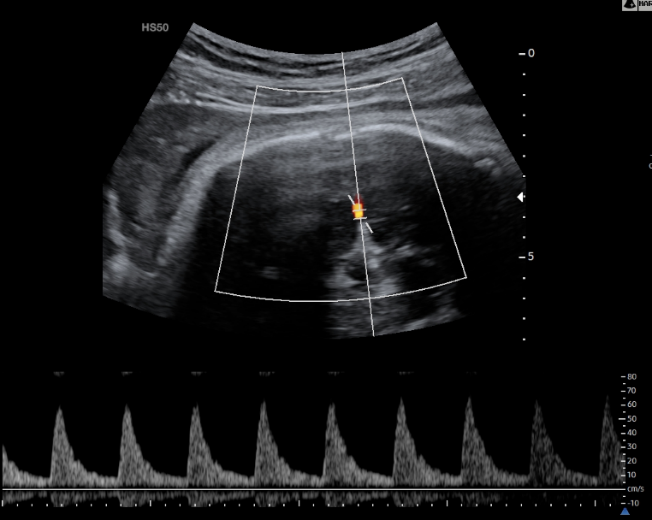

Doppler Ομφαλικής Αρτηρίας

Η Υπερηχογραφία Doppler στην Ομφαλική Αρτηρία θα μας δείξει εάν η τροφοδοσία του εμβρύου με αίμα και θρεπτικά συστατικά είναι επαρκής.

Εικόνα 03 – Φυσιολογική καμπύλη Doppler Ομφαλικής Αρτηρίας